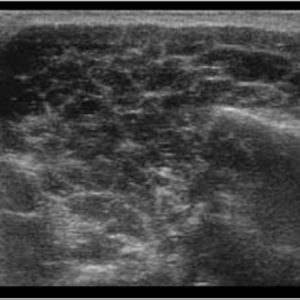

Bệnh Sjögren

Lượt xem: 201» 16-01-2021 -

Bệnh Sjögren

Lượt xem: 152» 16-01-2021 -

Bệnh Sjögren

Lượt xem: 162» 16-01-2021 -

Bệnh Sjögren

Lượt xem: 163» 16-01-2021 -

Viêm tuyến nước bọt

Lượt xem: 168» 16-01-2021 -

Viêm tuyến nước bọt

Lượt xem: 173» 16-01-2021